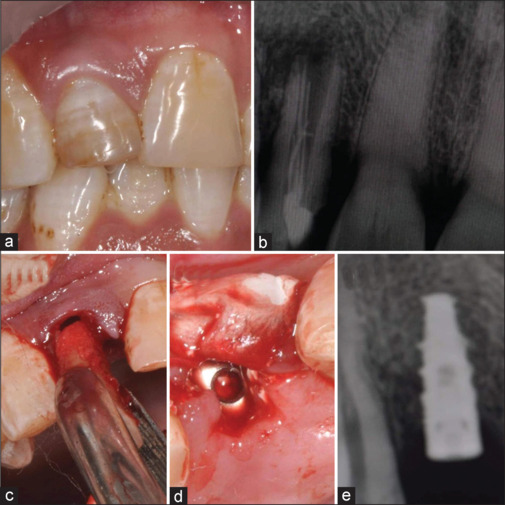

Background: Dental implants in fresh extraction sockets of the maxillary esthetic area are technique-sensitive procedures where retaining a buccal root segment can enhance periodontium preservation and esthetics. This study aims to compare marginal bone levels and esthetic outcomes between conventional immediate implant placement and the socket-shield technique in fresh maxillary extraction sockets.

Materials and methods: Twenty-four patients with type 1 extraction sockets were included in this randomized trial and assigned to either conventional immediate implant placement or the socket-shield technique. Implant survival, crestal bone levels, and pink esthetic scores (PES) were evaluated at 8 months (temporary prosthesis), 12 months, and 36 months (final crowns).

Results: All implant-supported restorations were successful within the study's observation period. The socket-shield technique showed significantly lower marginal bone loss (e.g. 1.40 ± 0.29 mm vs. 1.70 ± 0.36 mm at 36 months; P = 0.040) and superior PES (e.g., 10.50 ± 0.90 vs. 9.36 ± 0.98 at 36 months; P = 0.008) compared to the conventional technique. However, the technique's complexity underscores the need for expertise and careful execution to optimize tissue preservation in the maxillary esthetic zone.

Conclusion: The socket-shield technique better preserves hard and soft tissues around implant-retained prostheses than conventional implant placement in maxillary esthetic regions. Further studies with larger sample sizes and longer follow-up are required to validate these findings.